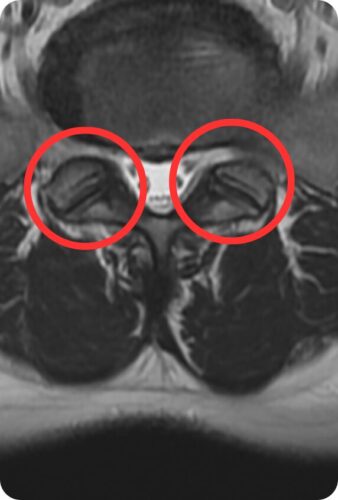

そして、絶望はこれだけではありませんでした。 別の角度(輪切り)の写真を見せられ、医師から衝撃の事実を告げられました。

医師:「ヘルニアだけじゃないね。ここ、骨が折れて離れてるよ」

これがL5 分離症の画像です。

赤丸の部分、骨のリングが途切れてしまっています。 医師によると、これは最近の怪我ではなく、若い頃の激しい運動や、長年の金属疲労の蓄積で骨が疲労骨折を起こして、そのまま固まらずに分離してしまった状態だそうです。